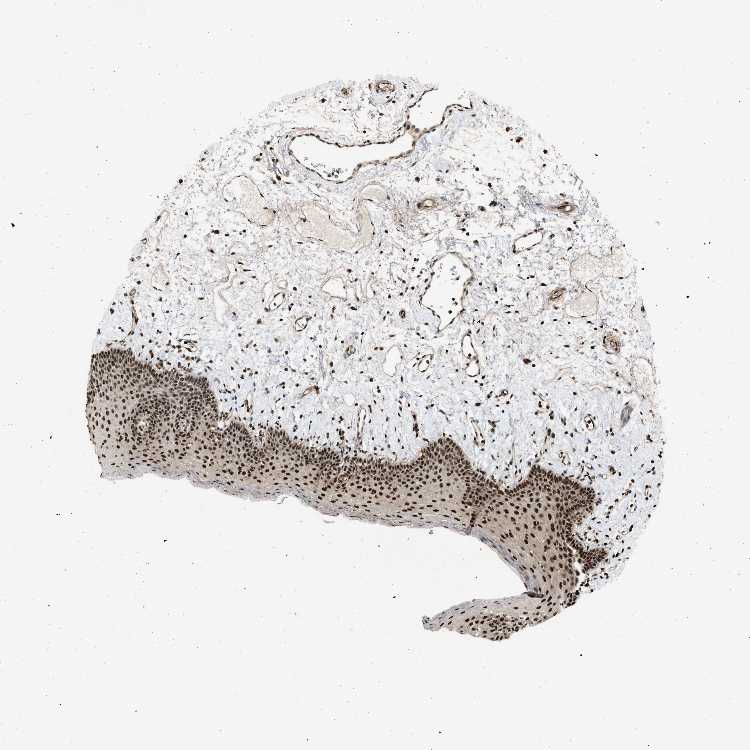

TISSUE PRIMARY DATA ORAL MUCOSA Show tissue menu

ORAL MUCOSA - Antibody stainingi

Antibody staining in the annotated cell types in the current human tissue is reported as not detected, low, medium, or high, based on conventional immunohistochemistry profiling in selected tissues. This score is based on the combination of the staining intensity and fraction of stained cells.

Each image is clickable and will lead to virtual microscopy that enables deeper exploration of all samples and also displays staining intensity scores, fraction scores and subcellular localization as well as patient and tissue information for each sample.

Antibody CAB018396

Squamous epithelial cells High